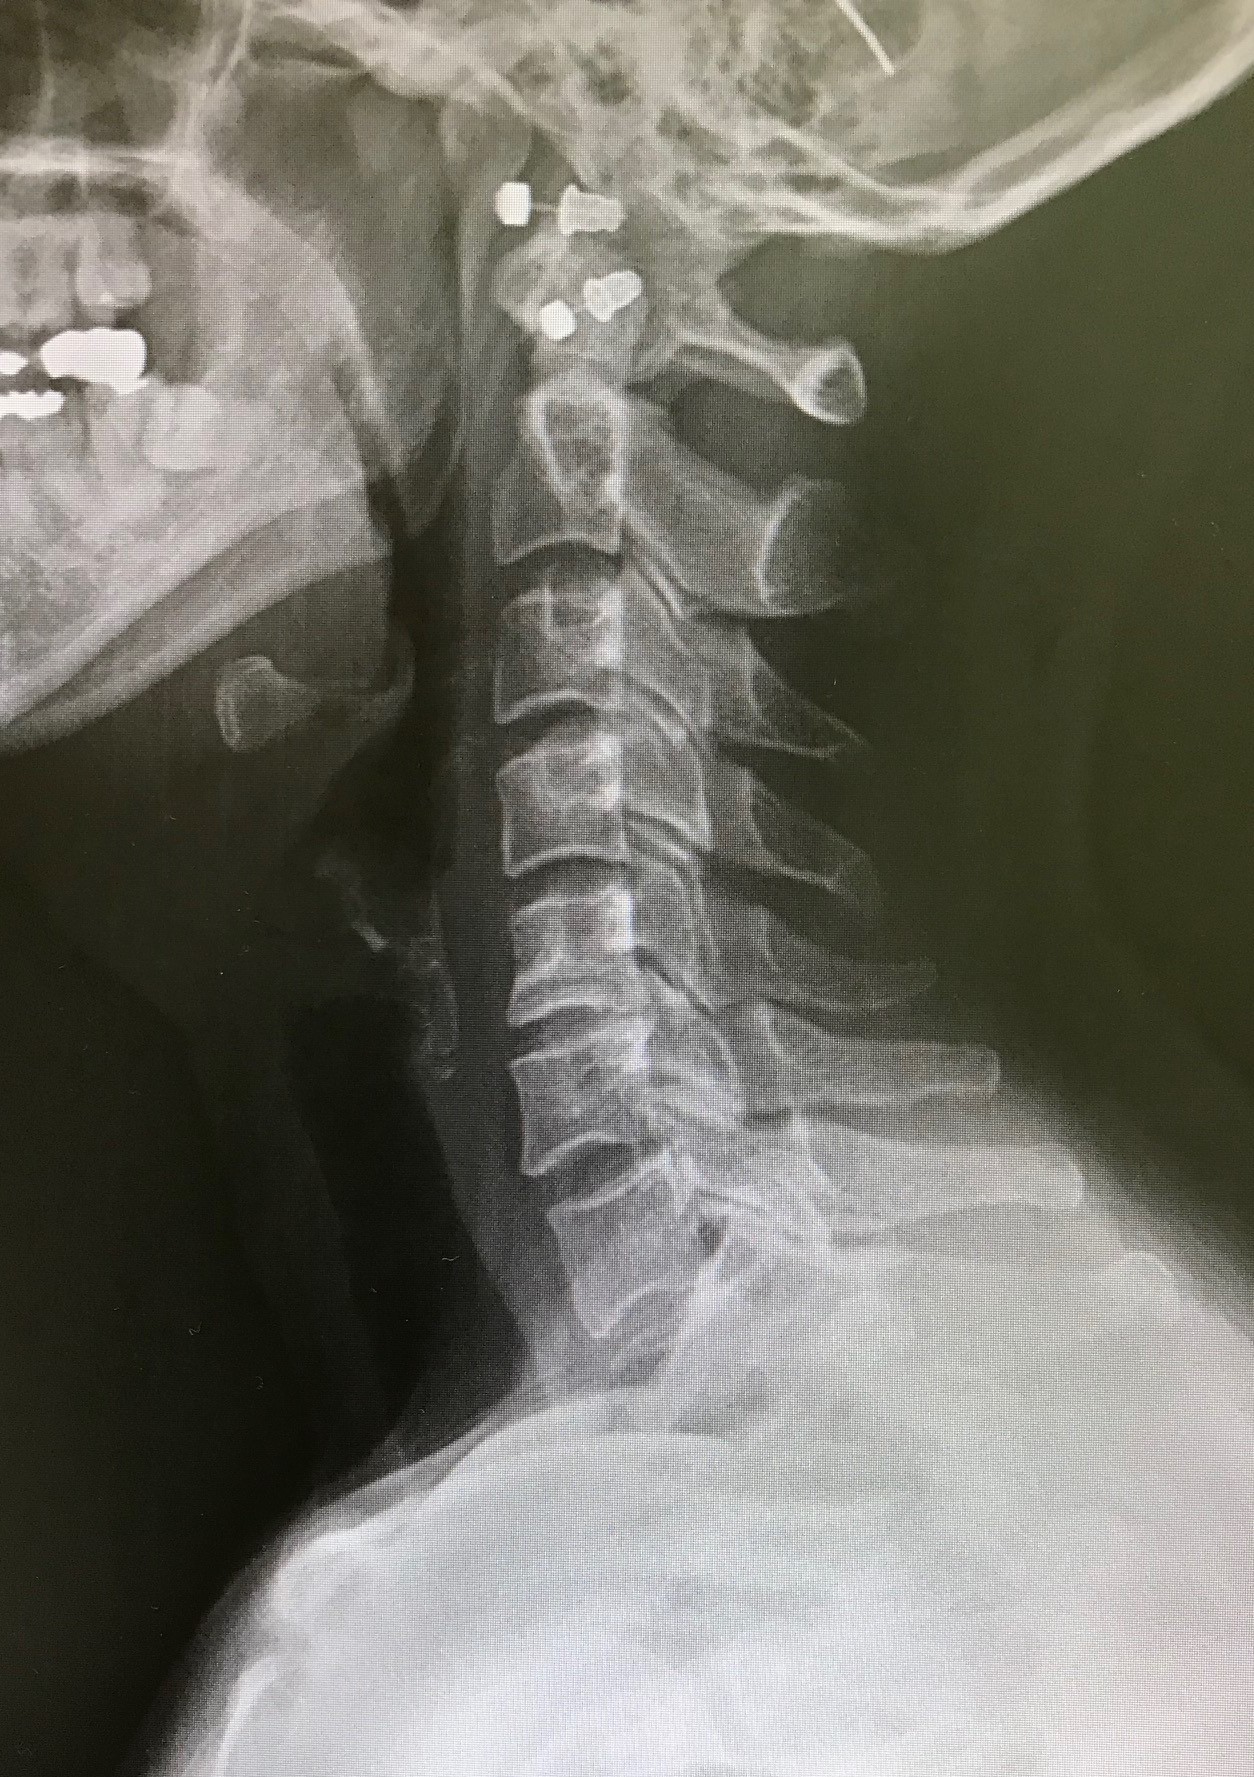

継続使用による変化の一例

ネックオアシスを継続使用した方の頸椎X線写真です。

使用前後で姿勢に変化が見られることがあります。

(※これは一例であり、すべての方に同様の変化が見られるわけではありません)

症例A 使用前

症例A 6か月使用後 50代女性・デスクワーク